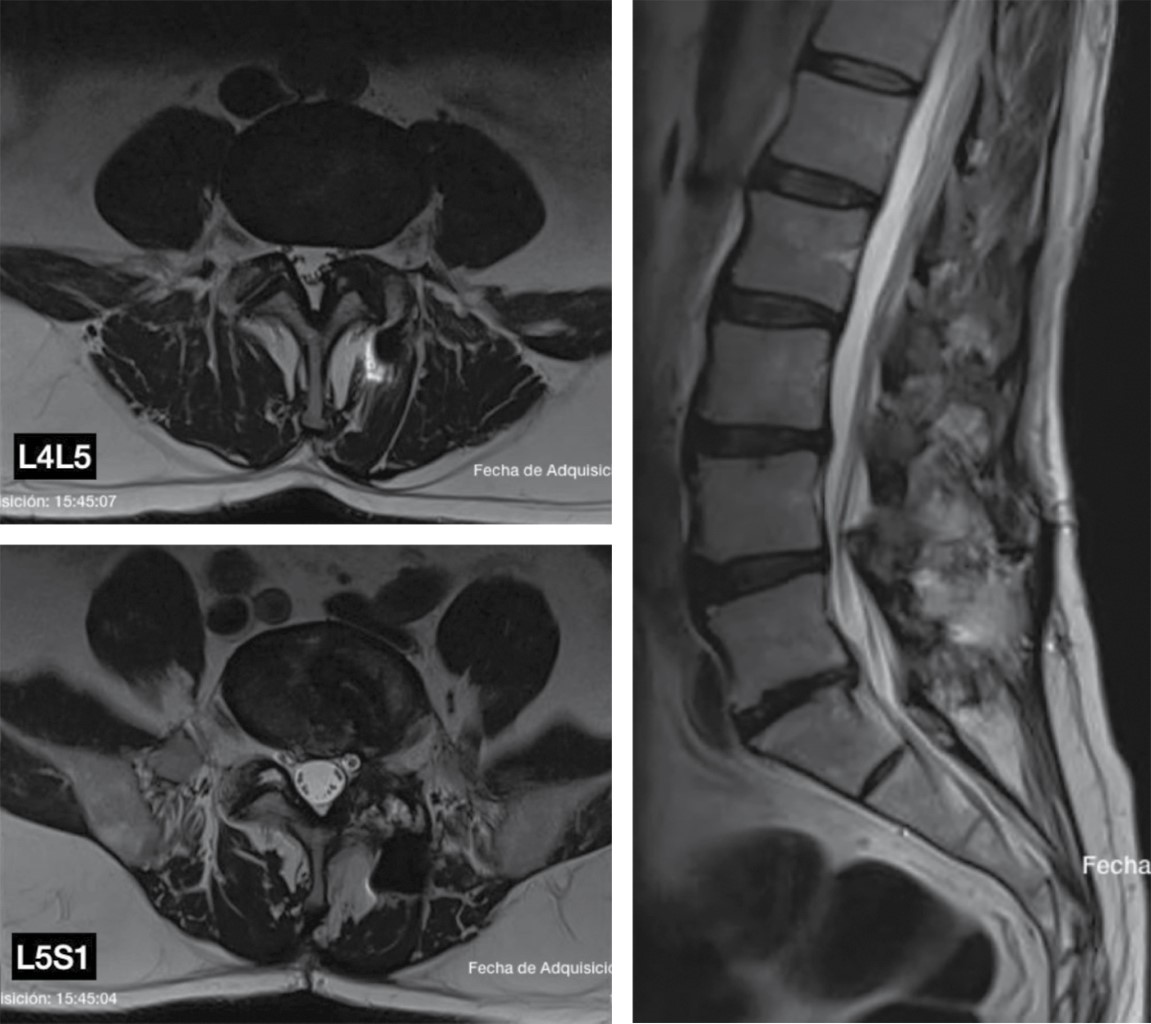

Se retira material de osteosíntesis, facetectomía L5-S1 izquierda para permitir distracción y preparación del espacio L5-S1. Abordaje lumbar anterior retroperitoneal, se retira la caja de PEEK (polieteretercetona) tipo banana; se realiza remodelación del osteofito posterior y preparación de plataformas. Se coloca caja ALIF más fijación anterior con dos tornillos. Se recoloca al paciente en posición prono; se realiza abordaje transforaminal L4-L5 para colocación de caja expandible y colocación de cinco tornillos percutáneos L4-S1 derecho, L4-L5 izquierdo. Se realiza control radiográfico y medición de parámetros espinopélvicos postquirúrgicos (Figura 4).

Figura 4